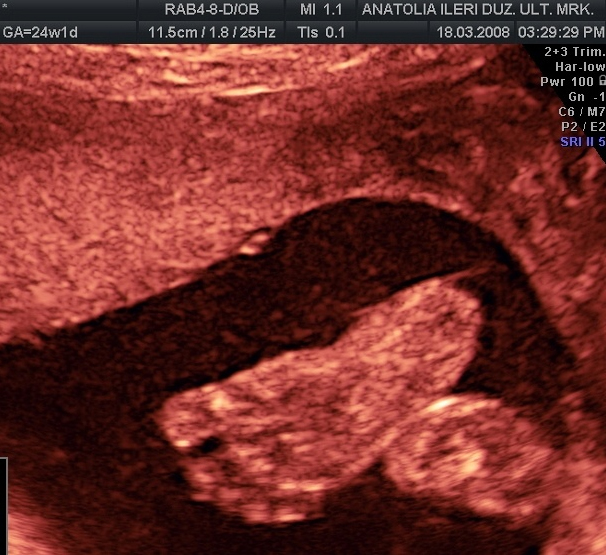

PARMAK EMME REFLEKSİ